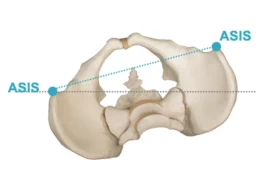

موقع الانحناء: الانحناءات القريبة من الرقبة أو القمة الصدرية العلوية (Cervical or Upper Thoracic) أكثر تأثيرًا على وضع الرأس.